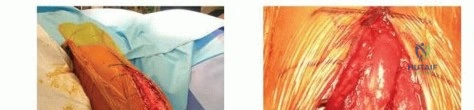

The Anterolateral Approach

The skin incision is made along a line connecting the coracoid process to the lateral epicondyle of the humerus. The length of the incision is dictated by the fracture pattern and the templated plate length. Subcutaneous tissues are dissected, taking care to identify and protect the cephalic vein, which can be retracted either medially or laterally depending on the exact proximal extent of the exposure.

The deep fascia is incised in line with the skin incision. The biceps brachii muscle is identified and mobilized medially, exposing the underlying brachialis muscle. At this juncture, the surgeon must decide on the specific handling of the brachialis muscle based on the fracture location.